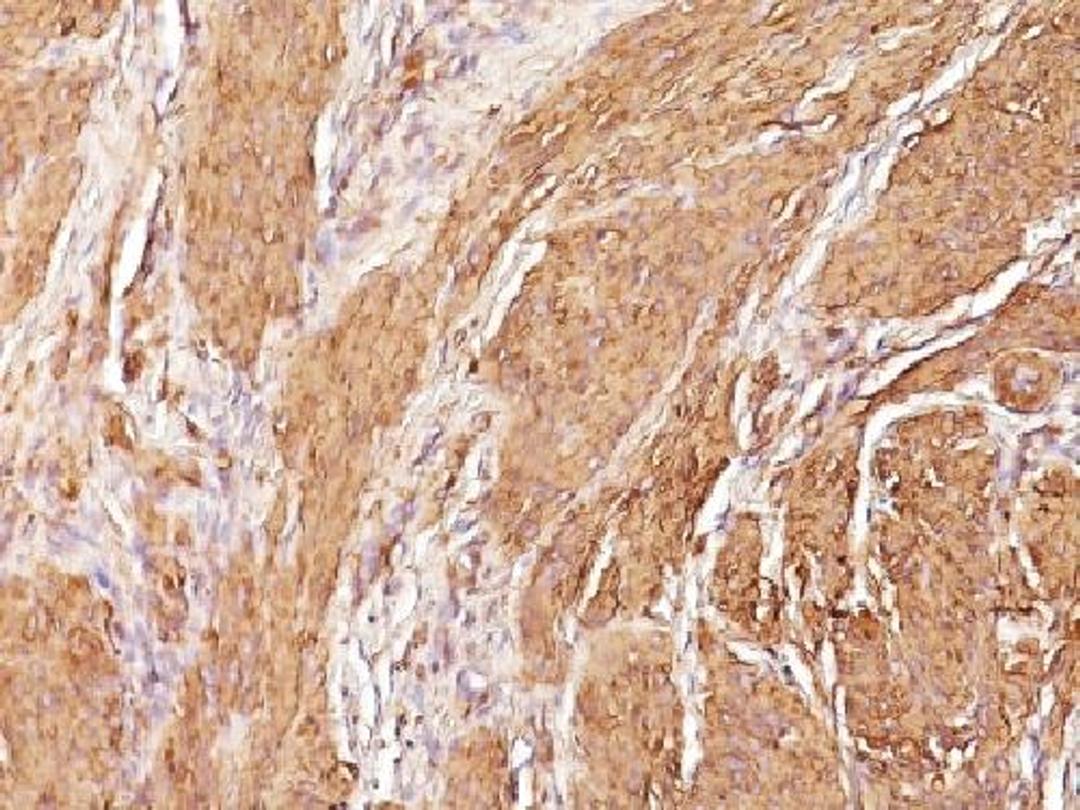

Mouse monoclonal antibody to KBA.62

- Immunohistochemistry (Paraffin-Embedded Sections) (IHC (P))